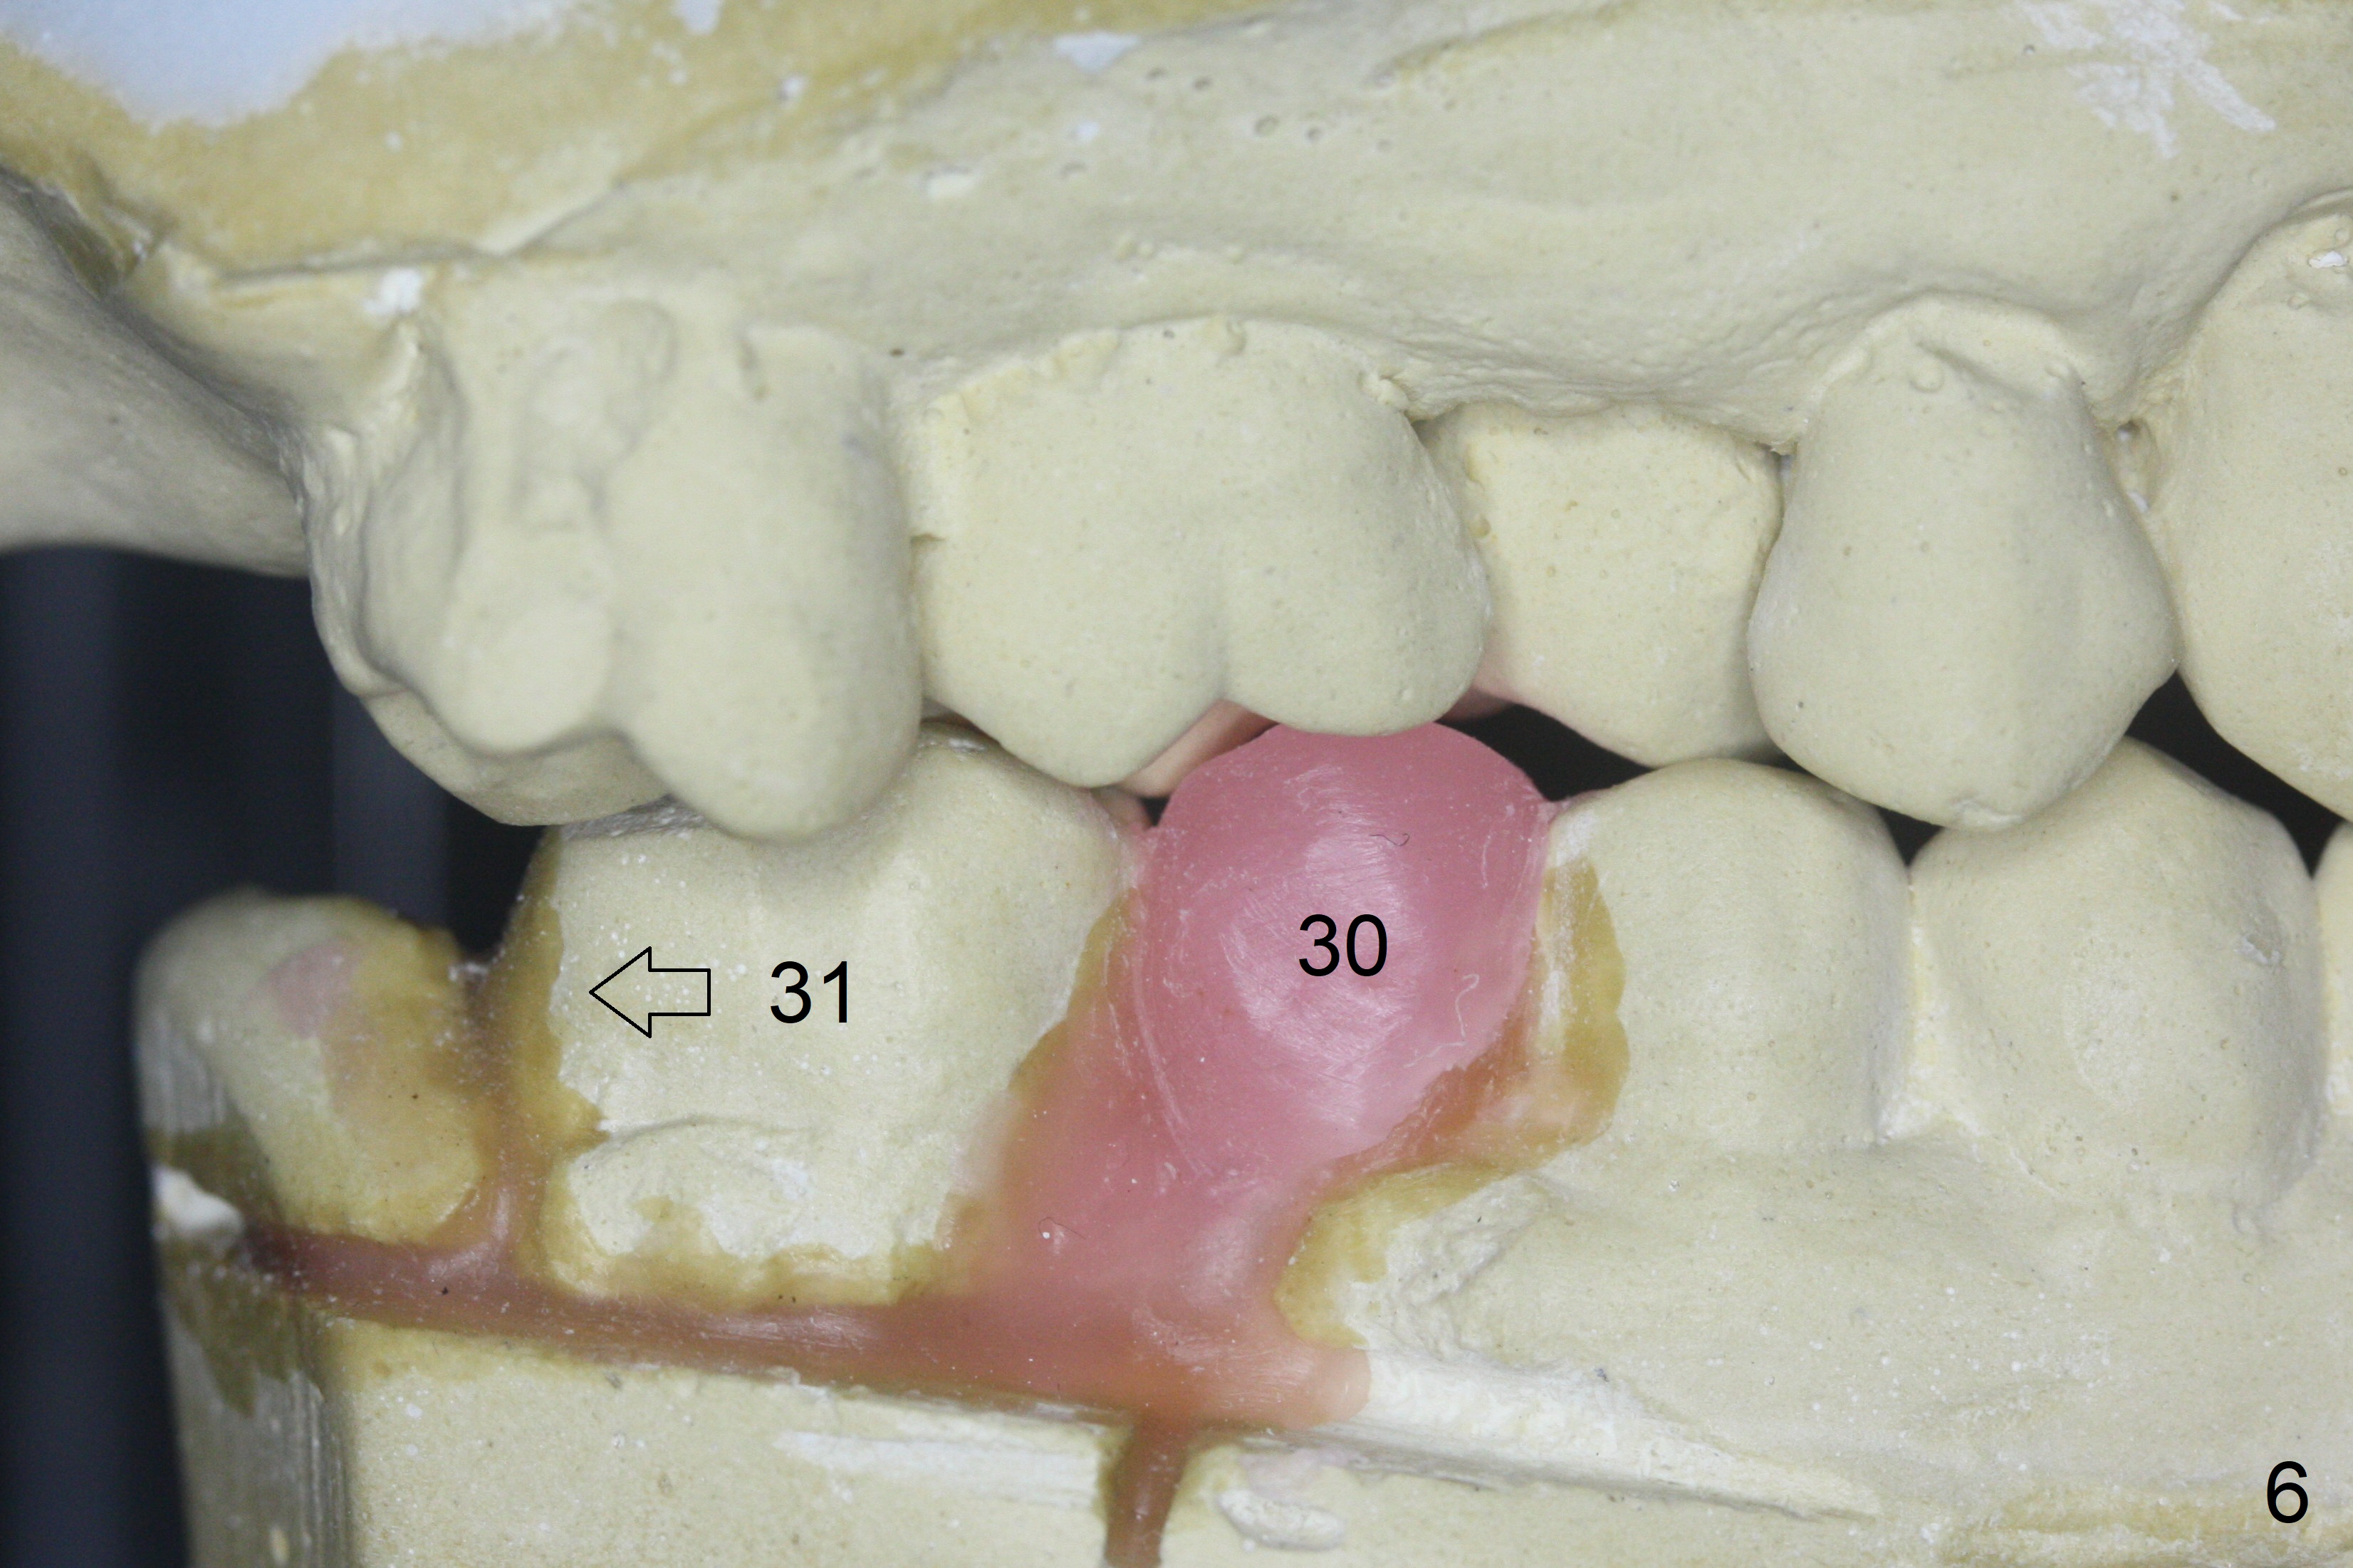

A 64-year-old man has discomfort with the lower left bridge and a loose tooth on the left (Fig.1). It appears that 4 implants are to be placed at #18,19,30 and 31. Since the tooth #4 and 13 are palatalized (Fig.2-4), the teeth #2 and 3 are mesialized (Fig.2 arrow). Besides, the ridge at #30 must be atrophic due to long termed edentulism. A small-diameter implant will be placed at #30 with premolar width (Fig.6-13), while the implant at #31 will be placed distal (arrow, as compared to Fig.2). To establish harmonious occlusion at provisional and final stages, the palatal slope of the mesiopalatal cusp of the tooth #2 will be adjusted (Fig.10).

Prepare 3 large pieces of gauze with the vasoconstrictor. If one of them is still too small for the socket, insert another piece of gauze without the vasoconstrictor for pressure hemostasis. Prepare PRF (x4) and Sinus Master Kit in case short stoppers are needed (Fig.12). CBCT taken immediately preop shows relatively wide ridge at #30 (Fig.14,16). The implant at #31 should be place in the distobuccal aspect of the socket (Fig.15,17): 2 mm drill with 7 mm stopper, 2.8 mm round drill at 5 mm (50 RPM) and 3.6 mm at 3 mm.